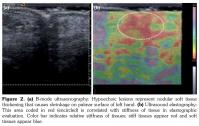

Active range of motion was measured with a finger goniometer which provided the following degrees of extension/flexion. Left hand: thumb metacarpophalangeal (MCP) joint -10/40, interphalangeal joint (IPJ) 0/40 and little digit MCP joint 0/80, proximal interphalangeal (PIP) joint 0/80. Right hand: thumb MCP joint 0/80, IPJ 0/80 and little digit MCP joint -20/40, PIP joint 0/40 (a negative value indicating lack of extension at MCP, PIP, and IPJ joints). The Hueston tabletop test was bilaterally positive (if the hand cannot be placed completely flat on the table with the palmar surface, the test is considered positive) and patient was diagnosed with DC. Patient’s medical history included high blood pressure, type 2 diabetes mellitus, and coronary artery disease. He had a five pack-year smoking history. Hematological examination and blood biochemistry results were normal. Ultrasonography and color Doppler imaging revealed thickening of both tendon sheaths and superficial palmar fascia with high vascularity and heterogeneity. There was no fluid in the tendon sheaths, which is a sign of tenosynovitis. The soft tissue thickening was also more superficial to the tendons located in the palmar fascia and deep surface of the dermis. The increased vascularity was interpreted as representing early signs of nodules and fibrosis which appear during the course of the disease. Nodular soft tissue thickening and thickened aponeurosis coded red on the color scale were harder when compared to the surrounding tissue, which supports fibrosis revealed in sonoelastographic examination (Figure 2, 3). We consulted plastic surgery but surgery was deemed to be appropriate for DC (thumb and little digit) after rehabilitation for post-traumatic ring finger. He was treated for bilateral hands with physical treatment program including contrast bath, ultrasound therapy, palmar massage, range of motion and stretching exercises for 15 days. Patient’s complaints decreased significantly. Also, improved hand functionality and increased range of motion were detected after treatment with the following degrees of extension/flexion. Left hand: thumb MCP joint 50, IPJ 20, little digit PIP joint 10. Right hand: little digit MCP joint 20, PIP joint 20.

Dupuytren’s contracture is usually diagnosed clinically. Magnetic resonance imaging or ultrasound may be useful for the differential diagnosis including tenosynovitis, trigger finger, ganglion cyst, soft tissue mass or for imaging of vascular complications.(9) Main findings are fibrous nodules and cord-like thickening in palmar fascia. The normal superficial palmar fascia appears as a thin echogenic line overlying the flexor tendons. At ultrasonographic evaluation, an elongated hypoechoic thickened plaque typically continuing with one or more of the flexor tendons and deep surface of the dermis is the pathognomonic sign of the disease. Early nodules are hypoechoic and typically hypervascular in Doppler imaging whereas older nodules are hyperechoic and non- hypervascular due to fibrosis and scar tissue.(9) Compression sonoelastography which is a newly developed technique as an adjunct to ultrasonographic examination can be used in several musculoskeletal disorders to evaluate the elasticity of muscle structures, tendons, ligaments or soft tissues.(10) However, the clinical utility still remains under investigation. Elasticity is represented by color coding where areas of stiff tissue appear red and soft tissues appear blue.

Elastography provides information regarding fibrosis. We showed that thickened aponeurosis and nodules had a firm structure with a predominant red color compared to the surrounding tissue in sonoelastographic findings of DC. Sonoelastography is a potential diagnostic tool which may differentiate both the acute and chronic findings in DC and provide information regarding differential diagnosis.